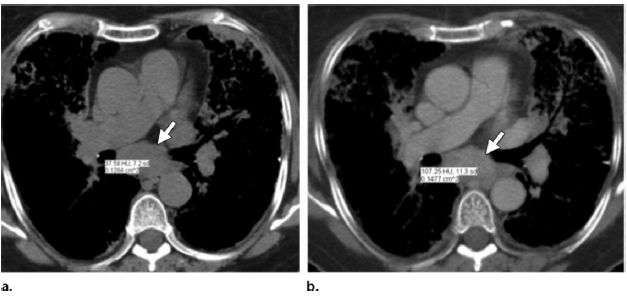

图5, 6 (5)患者,女,70岁,系统性淀粉样变性(AL)累及肺、胸膜及纵隔。(a)增强CT示气管隆突下淋巴结肿大。(b,c)左下叶肿块为淀粉样蛋白沉积物。斑点状实质钙化(图b和c箭头)也见于肺实质淀粉样变性。双侧胸腔积液

(图c),胸穿证实了胸膜淀粉样变性。(6)患者,男,63岁,多发骨髓瘤

及淀粉样变性。肺CT平扫

示双侧少量胸腔积液及气管隆突下淋巴结肿大。尽管无特异性,淋巴结为含淀粉样蛋白沉积物。